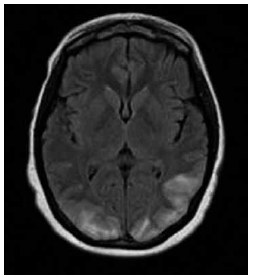

Garota de 13 anos de idade com diagnóstico recente de insuficiência renal crônica apresenta episódio de cefaleia, turvação visual e crise epiléptica tônico-clônica generalizada. A pressão arterial é de 180 x 100 mmHg. A ressonância magnética de crânio demonstra o achado a seguir.

O diagnóstico mais provável é